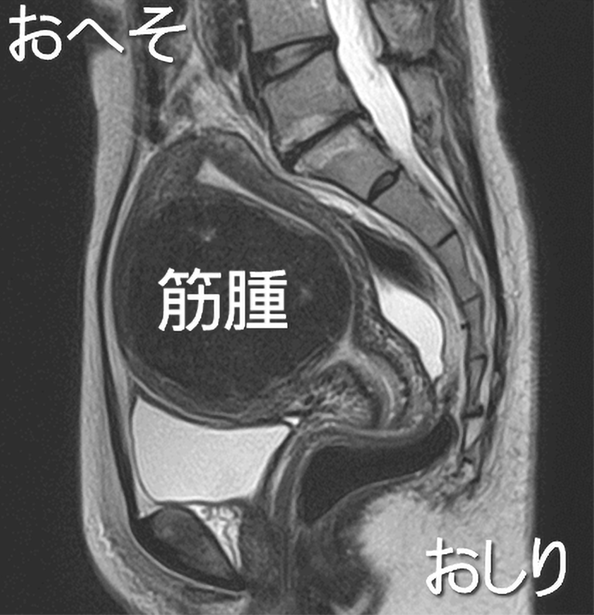

9cmの筋層内筋腫のMRIです。このような筋腫は、開腹または腹腔鏡では子宮を半分に割るように大きく切るので帝王切開になります。他の病院では開腹手術を勧められていましたが、腹腔鏡で摘出しました。難易度は高いですが子宮鏡での摘出も可能な筋腫です。子宮鏡なら自然分娩も可能です。